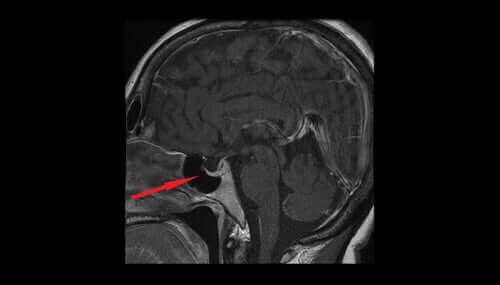

バゾプレッシンは、ADHや抗利尿ホルモンという名前でも知られています。このホルモンは、視床下部の大細胞核から分泌されます。分泌された後、脳下垂体後葉を通り、最終的に血流に入ります。腎臓が排出する水分量をコントロールすることで、体内の水分量の調節を助けます。今日の記事では、バゾプレッシンの様々な特徴と効果について見ていきましょう。

抗利尿ホルモンの値が低いと、腎臓は余分な水分を排出するでしょう。尿の量は増加し、水分不足や血圧の低下につながるでしょう。つまり、抗利尿ホルモンの値が低いということは、視床下部や脳下垂体のダメージや心因性多飲症の可能性が隠れているかもしれません。